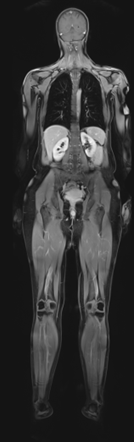

Whole-Body MRI Screening

While there are no reliable means of preventing the occurrence of cancer, we can often increase an individual’s chances of a cure by detecting the occurrence at an early stage. This is why we use whole-body MRI to scan the bodies of our patients for the presence of tumors, metastases, inflammation and other types of pathological tissue change.

Scope of the Whole-body MRI Exam

- Examination includes:

- Head and carotid arteries

- Neck and chest

- Abdominal and pelvic organs: liver, gallbladder, spleen, pancreas, kidneys, adrenal glands and urinary bladder

- Expressly for women: uterus, ovaries and fallopian tubes

- Expressly for men: seminal vesicles and prostate, including PSA test

- Lymph nodes

- Spine: orientational measurement above the lumbar spine; optionally cervical spine or thoracic spine

- Joints and soft-tissue structures: exploratory examination of the shoulders, hips, knees and ankles

- For technical reasons, the scope of the examination does not include the heart, the breasts and the colon.